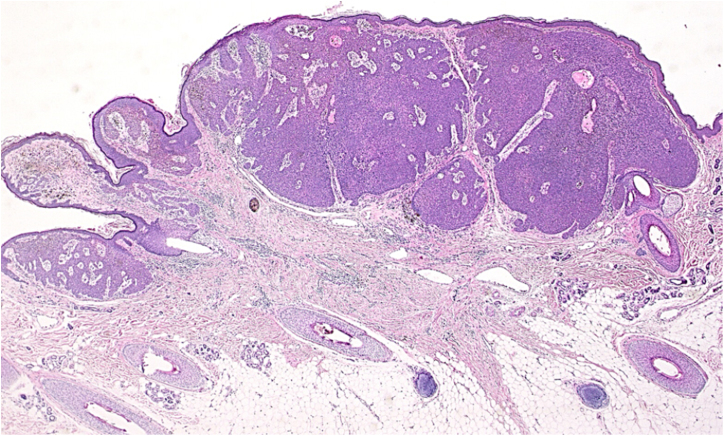

Figure 2.

Histopathological examination of the lesion revealed a nodular tumor extending from the epidermis into the mid-dermis (Hematoxylin-eosin stain, original magnification, 20×).